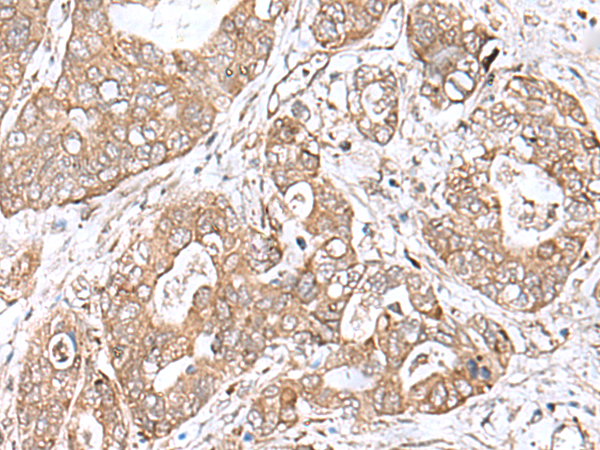

IHC positive control: |

Human gastric cancer |

IHC Recommend dilution: |

40-200 |